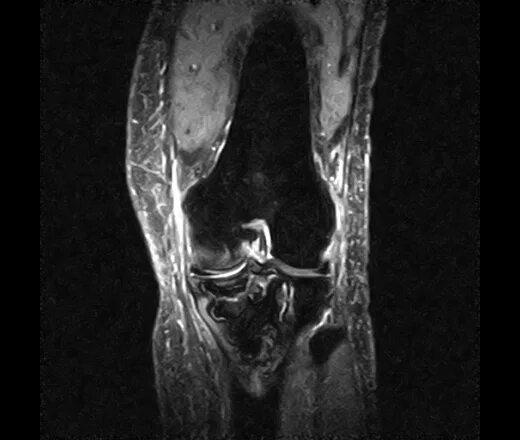

Мрт колена время